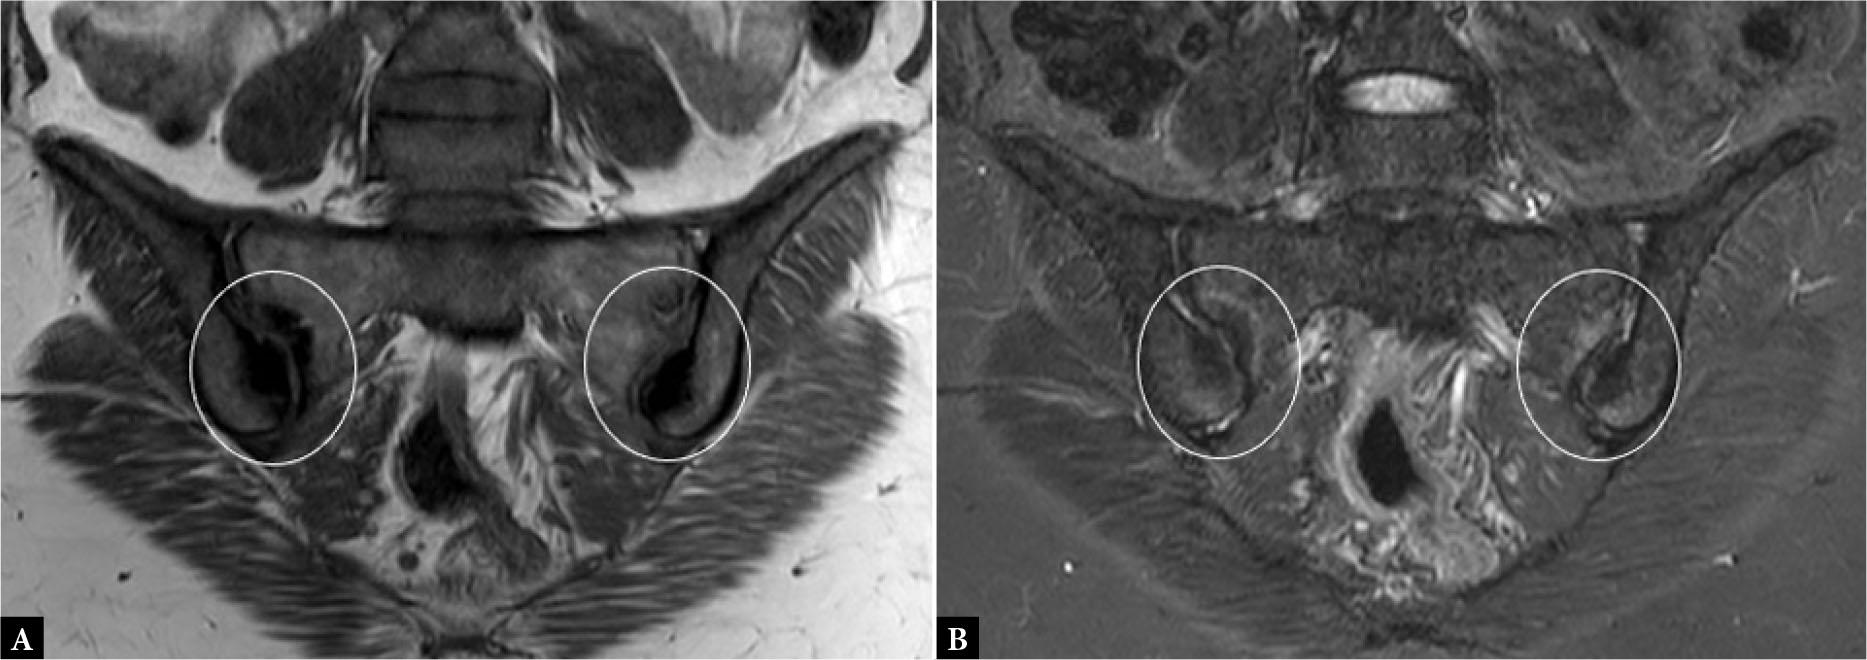

Fig. 18.

Sacroiliitis. Coronal oblique T1-W (A) and STIR (B) MR images of sacroiliac joints show bilateral symmetrical periarticular BME (hyperintensity within the circles in B) with areas of sclerosis (hypointensity within circles in A). There is a mild reduction in joint spaces and irregularity of articular marginsv